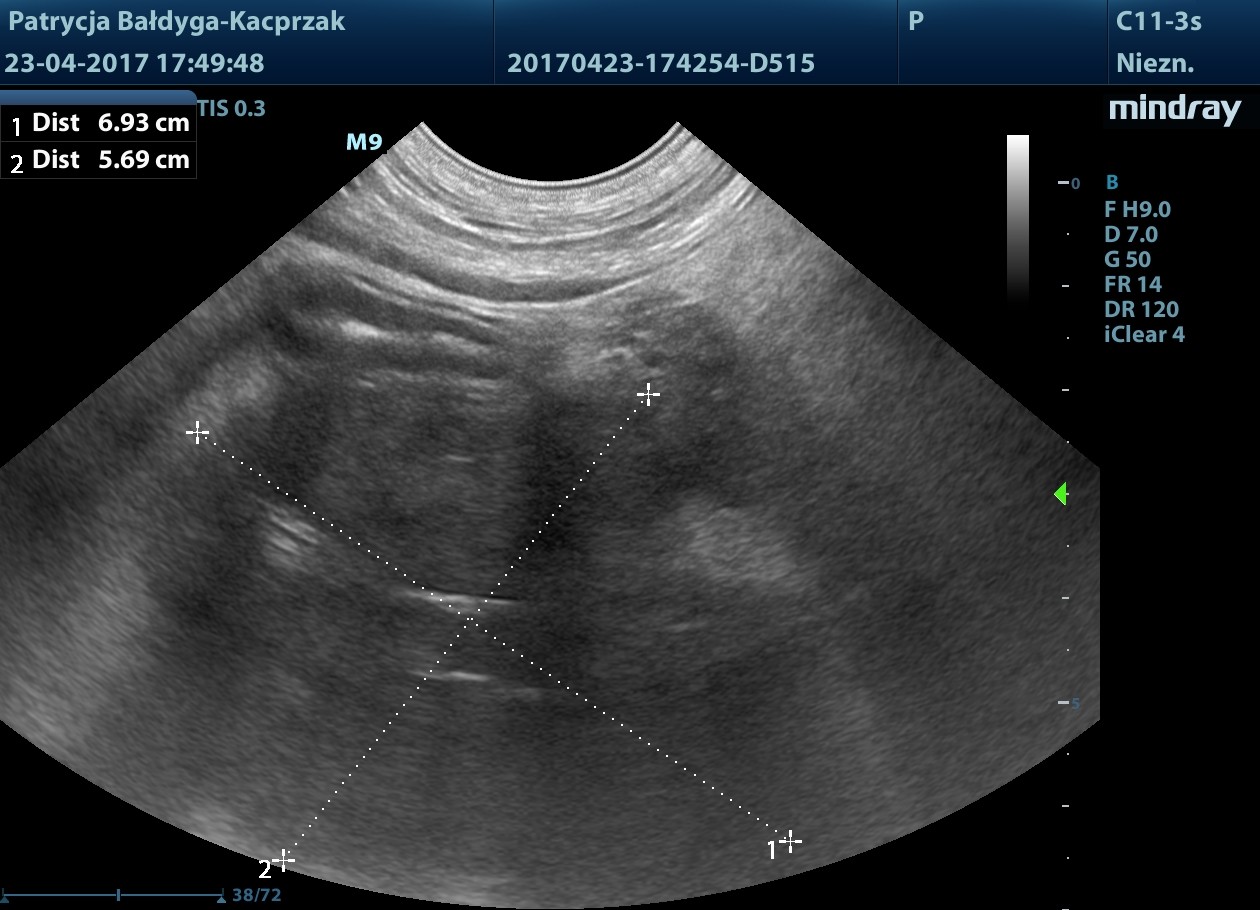

Kwiecień

Guz trzustki powiększył się

W płatach prawych wątroby widoczne nowe ogniska hiperechogenne, okrągłe ok. 13-31 mm, podejrzenie zmian metastatycznych